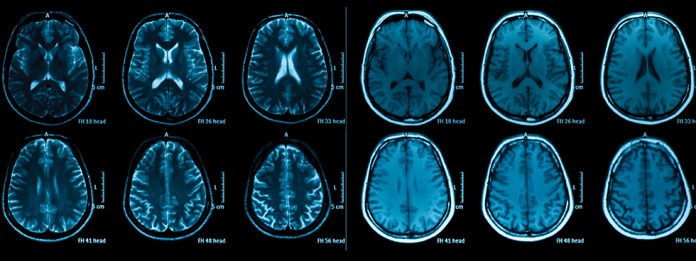

There are estimates that the human brain has about 100 Billion nerve cells and 1 Trillion glial cells (the cells that help the nerve cells out). The glial cells produce the materials, hormones and neurotransmitters (proteins, serotonin, dopamine) that are needed for the nerve cells to function. In the brain, these vital materials get shuttled around by the flow of the brain fluid (cerebral-spinal fluid) created in the brain that flows through channels (ventricles) inside the cholesterol jelly that holds our brain together. To maintain normal mental ability, you need only about 20 Billion (20%) of the nerve cells in the brain to be working and the brain fluids must keep flowing.